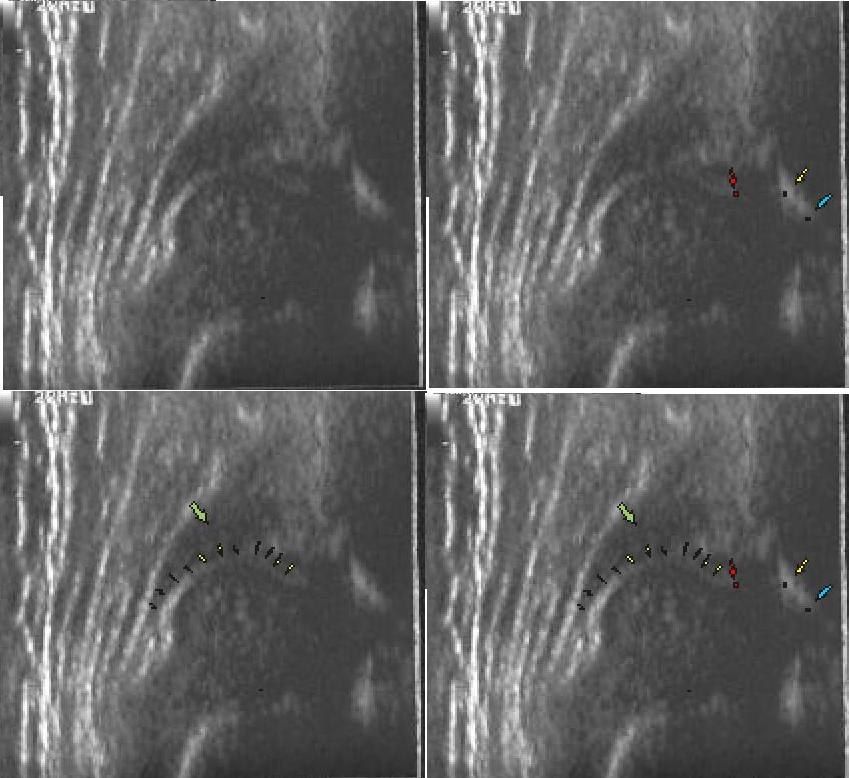

typIV powyzej zarys torebki zaznaczony kropkami widac charakterystyczna muldę głowa straciła kontakt z panewka, przesuneła sie w stosunku do niej doogonowo tzn szczyt paneki jest poniżej szczytu głowy

poniżej różnica między obrazem a pomiarem automatycznym kątów przez aparat usg

( w wywiadzie objaw Ortholaniego po urodzeniu zalecno kontrolę ortopedyczna za3tyg.)

Typ D(kąt jak Typ IIa) typ IIA (kąt I) dziecko 3 tygodniowe pomiar katów @ i B przez program w aparacie usg

po następnej wyznaczonej kontroli za 2miesiące w 3m.ż typ IV i I

typ IIIa poniżej ten sam staw na gorszym aparacie usg

typ IIIa 10 dzien życią strzałka żółta brzeg wtórnej płytkiej panewki do pomarańczowej strzalki ,to nie jest kąt @ jesli go obliczymy to bedzie powyżej 70 stopni ale głebokośc paneki jest nieadekwatna do wielkości głowy ok 1/5

typ IIIb 8 tyg. ze zniszczonym dachem chrzestnym zaznaczony pomarańczowymi strzałkami

obok typ IIa z okrągłym brzegiem kostnym i ubytkiem w panewce prawie 50%(strzałki żółte i pomarańczowe);i pozostała płytka panewka ale o dobrym nachleniu kat @ dachu kostnego 75 stopni ale z to nie może być biodro prawidłowe typ I z takim brakiem brzegu kostnego,trzeba uważać

musimy troche ściąć brzeg kostny tak jak pokazuje druga linia fioletawa (wyższa); nizsza fioletowa błędnie w tym stawie wkreślona to dobrze rokowniczo że brzeg kostny mimo dużego braku jest ostro zarysowany ale nie jest to prawidłowa panewka typ GN obustronie(3 tyg.) dolny sie pogorszył (dwa miesiace póżniej)głowa sie wysuwa,